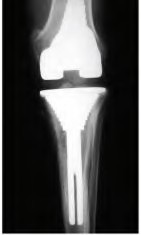

Which of the following statements best describes the surgical principle of true kinematic alignment in total knee arthroplasty?